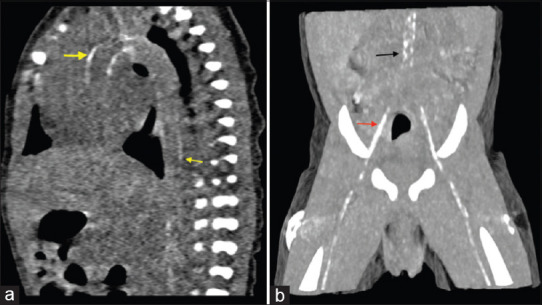

Generalized arterial calcification of infancy is a rare entity with poor fetal and postnatal outcomes and high morbidity in survivors. Half of the cases are diagnosed intrauterine due to hemodynamic compromise, and the associated manifestations pose unique management challenges. We hereby report an account of a fetal diagnosis in a referral for hydrops with postnatal evaluation and management.